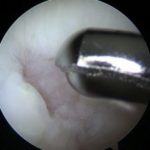

Articular cartilage damage in the knee (left). The cartilage damage after treatment with microfracture(right).